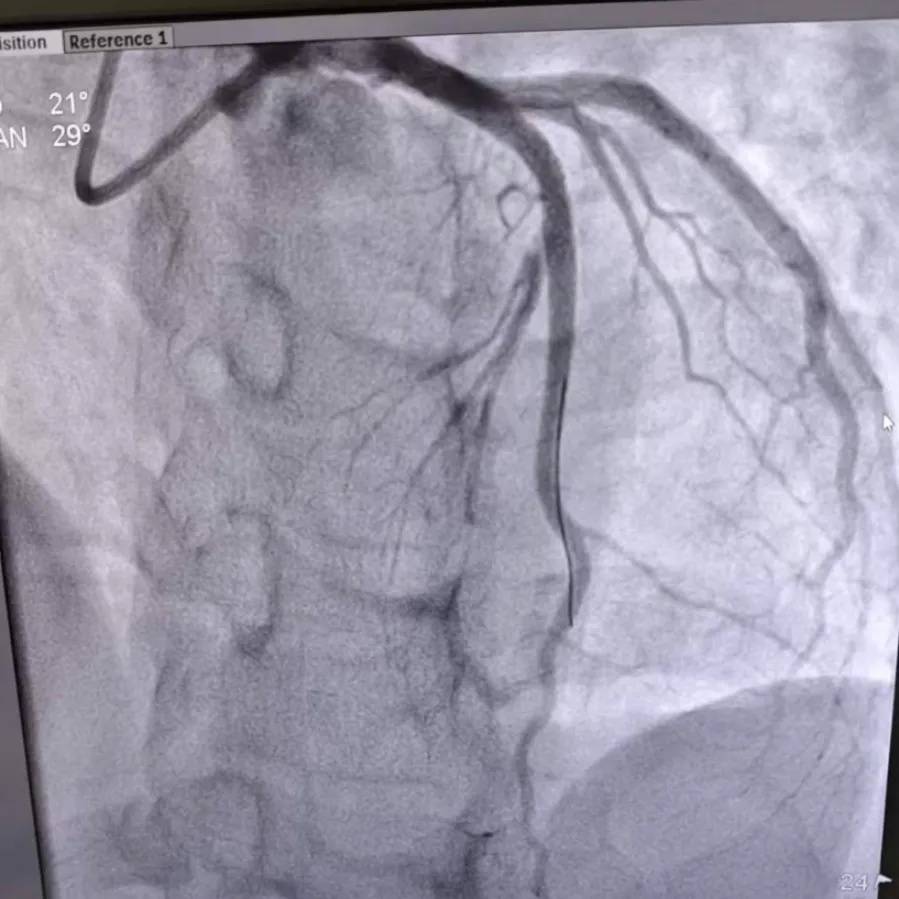

术后造影

面对万分危急的情况,心血管内科团队争分夺秒,通过血栓抽吸术清除“堵塞”,精准植入支架,及时打通了闭塞的血管。

随着血管的畅通,林先生的胸痛症状迅速缓解。